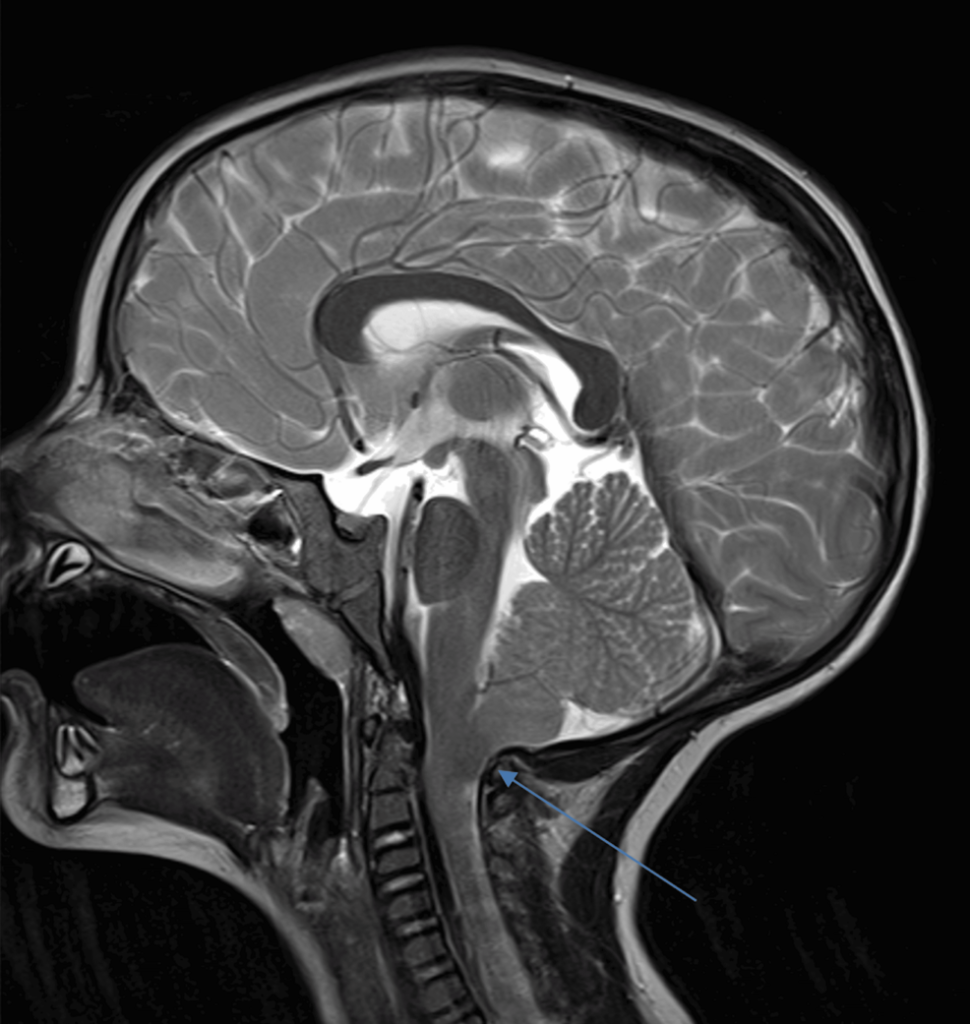

Magnetic Resonance Imaging (MRI) is the primary diagnostic tool for Arnold–Chiari malformation. The evaluation process includes:

- MRI of the brain and cervical spine

- Assessment of cerebrospinal fluid flow

The goal is to assess not only the anatomical displacement but also its functional consequences